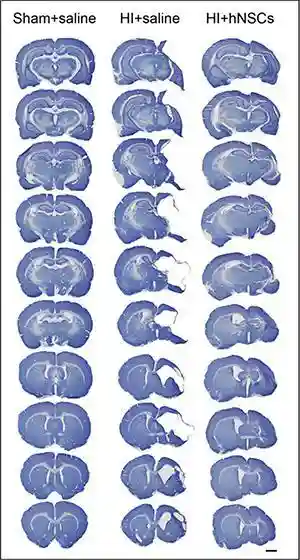

郭教授的团队还发现,人源神经干细胞能够在3-24小时之内广泛分布于大脑损伤区,持续42天的疗效观察证明神经干细胞可长期存活于大脑(图1);并完全自主和有效的分化为神经元和星形胶质细胞,用以弥补受损的神经细胞(图2);能够很好的修复因缺血缺氧导致的大脑组织缺失和白质损伤(图3)。

图3、能够很好的修复因缺血缺氧导致的大脑组织缺失和白质损伤